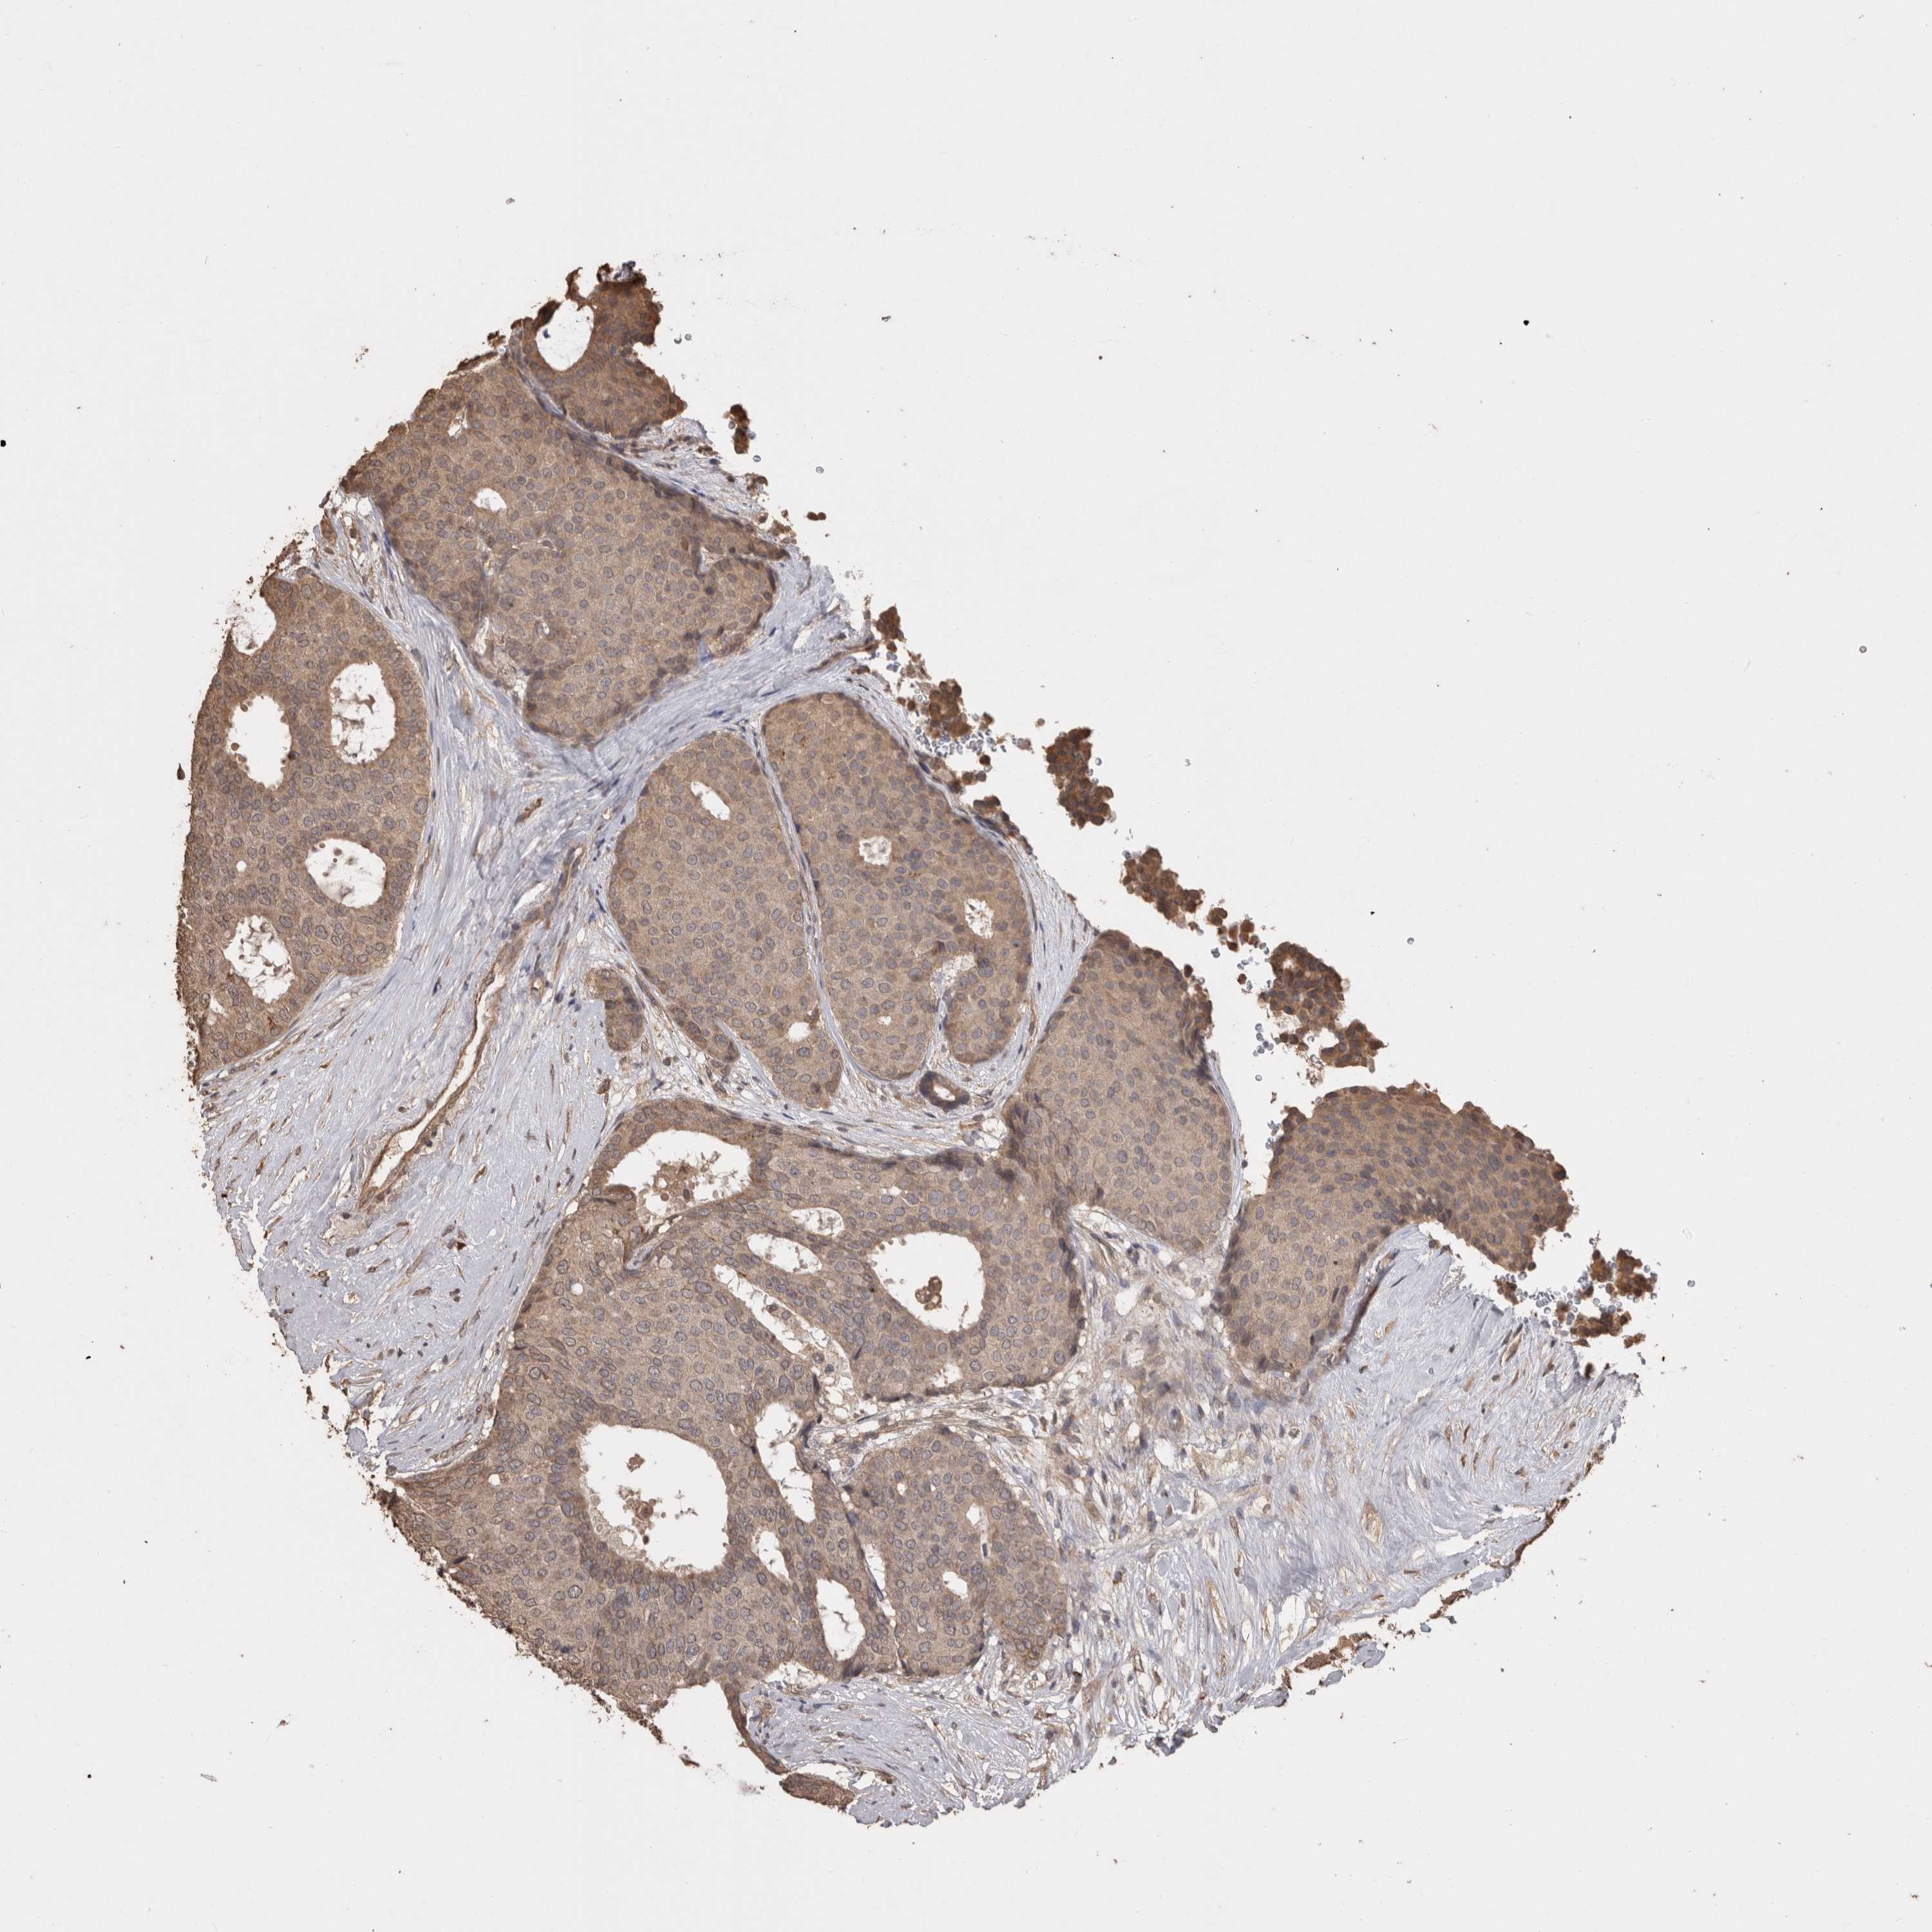

CANCER BREAST CANCER Show tissue menu

Breast cancer

Human cancer